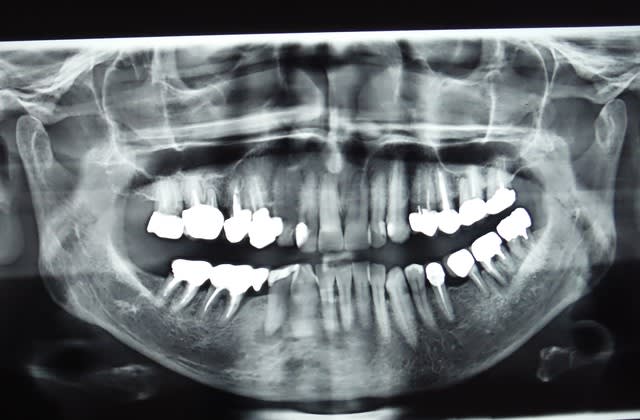

Sur-traitement?

En tout cas c'est bibi qui va si coller.

Dscf1270  2  rjhtsk - Eugenol

Et celui là, fractures de 11 et 21.

4 monobloques à tenons solidarisées!!! Avec 22 et 12 non étanches, carie sous l'infrastructure, vu les axes pas étonnant, résultat 12 et 22 à exo, fracture pour 12. La 21 est bien sympa aussi et financièrement les implants... pas simple.

Ah le travaille n'a pas 4 ans et le dentiste est parti à la retraite, donc encore pour bibi.